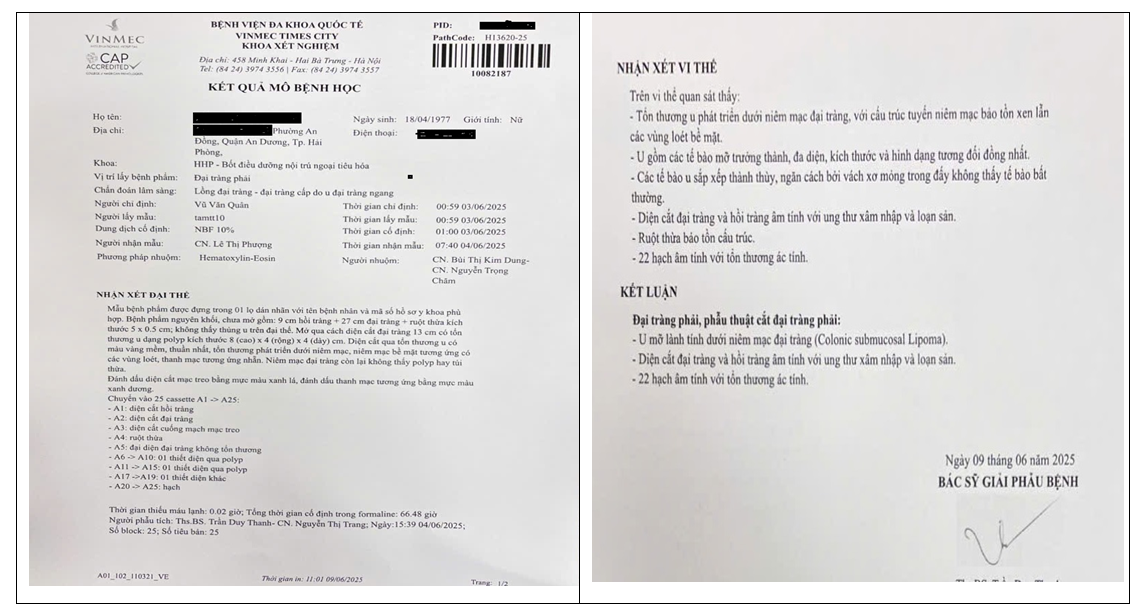

GIẢI PHẪU BỆNH

Kết quả xét nghiệm đại thể cho thấy một khối có màu vàng nhạt (u mỡ) có giới hạn rõ, kích thước 80 x 40×40 mm. Kết quả vi thể cho thấy khối u này phù hợp với u mỡ, được bao bọc bởi mô mỡ thùy bình thường chứa các tế bào mỡ đơn thùy, ngăn cách bởi vách xơ mỏng (Hình 4). Chiều dài đại tràng sau khi cắt bỏ 270 mm và niêm mạc đại tràng không có gì bất thường. Các hạch xét nghiệm âm tính với tổn thương ác tính.

Hình 4.